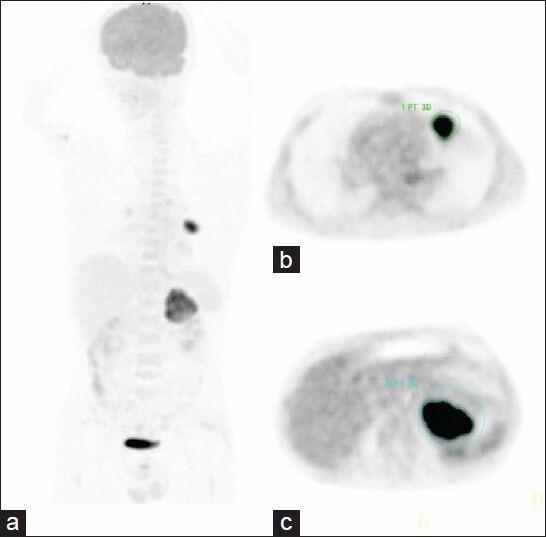

To assess the prognostic value of maximum standardized uptake value (maxSUV) of the primary tumor (maxSUVpt), maxSUV of whole-body tumors (maxSUVwb) and sum of maximum standardized uptake value (sumaxSUV) measured by the sum of maxSUVs of the primary tumor, metastatic lymph nodes, and metastatic lesions per each organ on fluoro-D-glucose-positron emission tomography/computed tomography in advanced non-small cell lung cancer (NSCLC). Eighty-three patients (49 male, 34 female) with advanced NSCLC were enrolled. Seventeen patients had Stage IIIA, 21 Stage IIIB, and 45 Stage IV. maxSUVpt, maxSUVwb, sumaxSUV, age, gender, tumor-cell type, T stage, N stage, overall stage, primary tumor size, and specific treatment were analyzed for correlation with overall survival. Median follow-up duration was 13 months. Fifty patients were dead during a median follow-up time of 11 months and 33 patients were alive with a median time of 15 months. Univariate analysis revealed that overall survival was significantly correlated with sumaxSUV (≥35 vs. <35, P = 0.004), T stage (T4 vs. T1-T3, P = 0.025), overall stage (IV vs. III, P = 0.002), gender (male vs. female, P = 0.029) and specific treatment (no vs. yes, P = 0.011). maxSUVpt and maxSUVwb were not correlated with overall survival with P value of 0.139 and 0.168, respectively. Multivariate analysis identified sumaxSUV, T stage, gender, and specific treatment as independent prognostic indicators. Patients with a sumaxSUV of ≥35 were 1.921 times more likely to die than those with a sumaxSUV of < 35 (P = 0.047). Median survival time was 14 months for patients with sumaxSUV ≥ 35 compared with 20 months for those with sumaxSUV < 35. In patients with metastatic NSCLC, sumaxSUV with cut-off of 35 was much more significant for survival prognosis (P = 0.021). sumaxSUV is a new prognostic measure, independent of tumor stage, gender, and specific treatment in advanced NSCLC. sumaxSUV may be better than maxSUVpt and maxSUVwb in prediction of survival. A large prospective cohort study is necessary to validate these results.

评估氟代脱氧葡萄糖正电子发射断层扫描/计算机断层扫描中,原发性肿瘤的最大标准化摄取值(maxSUVpt)、全身肿瘤的maxSUV(maxSUVwb)以及通过原发性肿瘤、转移淋巴结和每个器官转移病灶的maxSUV总和测得的最大标准化摄取值总和(sumaxSUV),在晚期非小细胞肺癌(NSCLC)中的预后价值。纳入83例晚期NSCLC患者(49例男性,34例女性)。17例为IIIA期,21例为IIIB期,45例为IV期。分析maxSUVpt、maxSUVwb、sumaxSUV、年龄、性别、肿瘤细胞类型、T分期、N分期、总分期、原发性肿瘤大小和具体治疗与总生存期的相关性。中位随访时间为13个月。50例患者在中位随访时间11个月时死亡,33例患者存活,中位时间为15个月。单因素分析显示,总生存期与sumaxSUV(≥35 vs. <35,P = 0.004)、T分期(T4 vs. T1-T3,P = 0.025)、总分期(IV vs. III,P = 0.002)、性别(男性vs.女性,P = 0.029)和具体治疗(否vs.是,P = 0.011)显著相关。maxSUVpt和maxSUVwb与总生存期无相关性,P值分别为0.139和0.168。多因素分析确定sumaxSUV、T分期、性别和具体治疗为独立预后指标。sumaxSUV≥35的患者死亡可能性是sumaxSUV<35患者的1.921倍(P = 0.047)。sumaxSUV≥35的患者中位生存时间为14个月,而sumaxSUV<35的患者为20个月。在转移性NSCLC患者中,sumaxSUV临界值为35时对生存预后的影响更为显著(P = 0.021)。sumaxSUV是一种新的预后指标,独立于晚期NSCLC的肿瘤分期、性别和具体治疗。在预测生存期方面,sumaxSUV可能优于maxSUVpt和maxSUVwb。需要进行大规模前瞻性队列研究来验证这些结果。